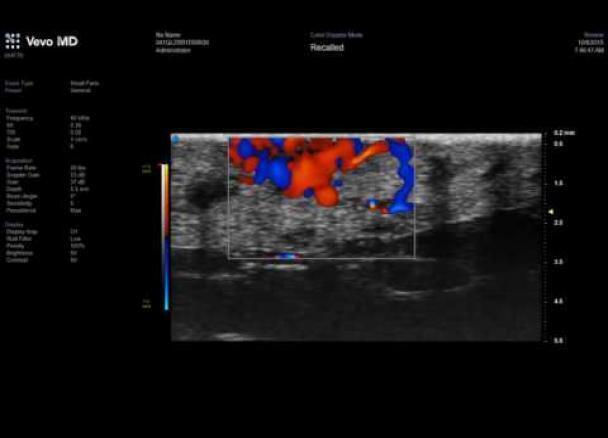

VEVO MD UHF 70 vena Superficial con flujo de color 6568

Vevo MD UHF 70 Sag Superficial Mass with underlying vein and colour flow 6556